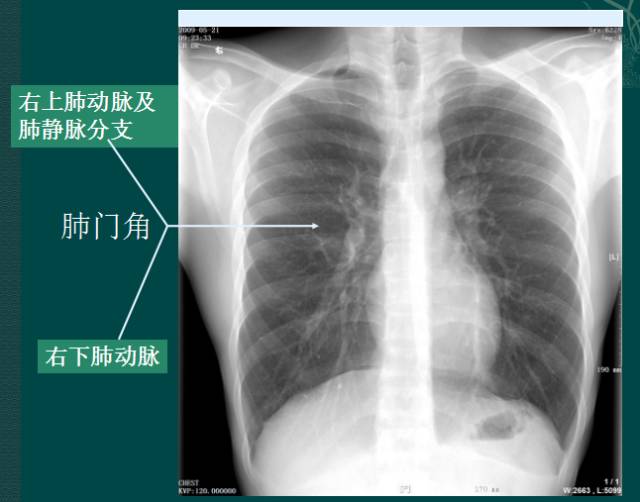

4. 肺门的大小和位置

X线肺门指肺动脉、肺叶动脉、肺段动脉、伴行支气管以及肺静脉构成。

右肺门可分为上、下两部。上部约占1/3,由上肺静脉、上肺动脉及下肺动脉后回归支构成。上肺静脉下后干构成右上肺门的外缘;右肺门下部 约占2/3,由右下肺动脉干构成,其正常宽度不超过15mm,沿中间段支气管外缘平行向外下走行。右肺门上、下部相交形成一钝的夹角,称肺门角,正常该角顶清晰。如下图

左肺门亦分为上、下两部。上部由左肺动脉及其分支、左上叶支气管和左上肺静脉及其分支构成;下部由左下肺动脉及其分支构成,常被心影所遮盖。